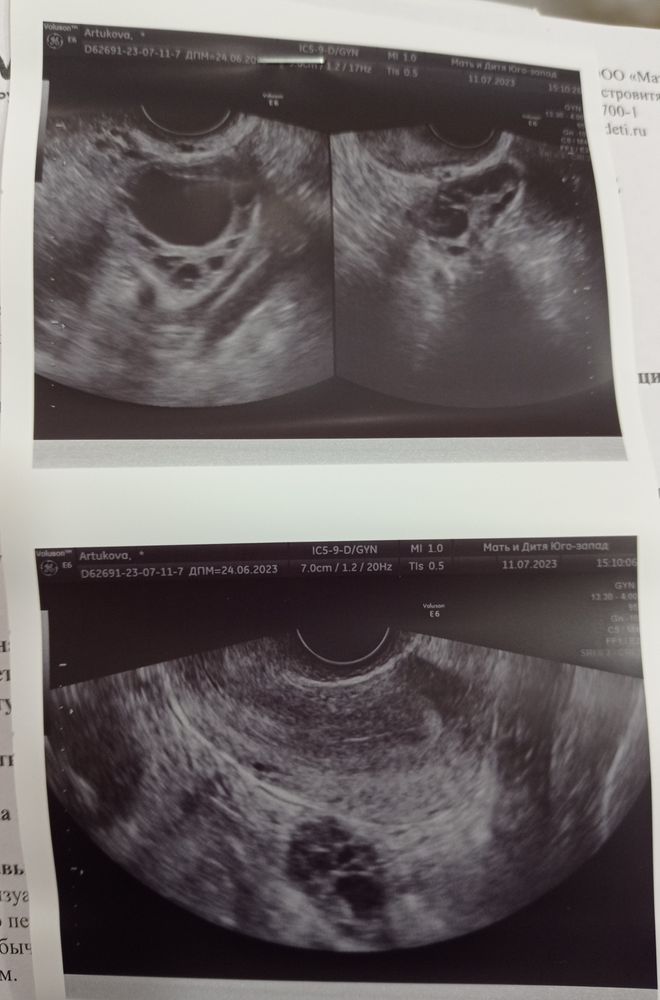

Сделала УЗИ по рекомендации репродуктолога, так как она в отпуске. На УЗИ сказали, что 2 фаза уже идёт, и анэхогенное образование 26 мм. Под вопросом жёлтое тело или киста жёлтого тела. Уточнила у врача, она сказала, что не может точно сказать была овуляция или нет. Репродуктолог написала сдать прогестерон и эстрадиол, жду результатов теперь. По тестам тишина была, делала их 2 раза в день.

Может у кого есть опыт, могла ли быть овуляция или фолликул не лопнул?

Эм...вроде как киста жёлтого тело - это и есть жёлтое тело, только большего размера. То есть неважно, жёлтым телом это назвать или кистой, овуляция все равно скорее всего была (если только это не киста, сохранившаяся с прошлого цикла).

Екатерина, нет, это не с прошлого цикла точно, я на стимуляции. Но мне никто точно не сказал, что овуляция была(